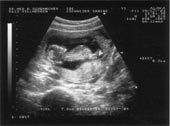

sehr früh. Hier der erste photographische Beweis meines frühen

Beginns.

Selbst für ungeschulte Augen ganz klar zu sehen wie ich einen Rock'n

Roll Basslauf auf der Nabelschnur zupfe.